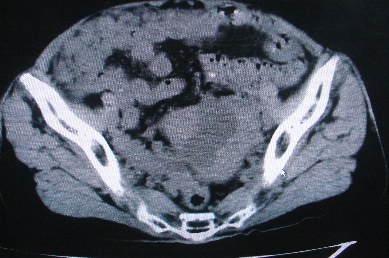

以下是引用卜一在2007-4-30 15:29:00的发言:[br]子宫明显增大,不规则,子宫壁不规则增厚,子宫腔明显缩小,子宫右侧软组织团块与子宫关系密切,内见低密度坏死区。考虑:子宫癌并周围侵润。